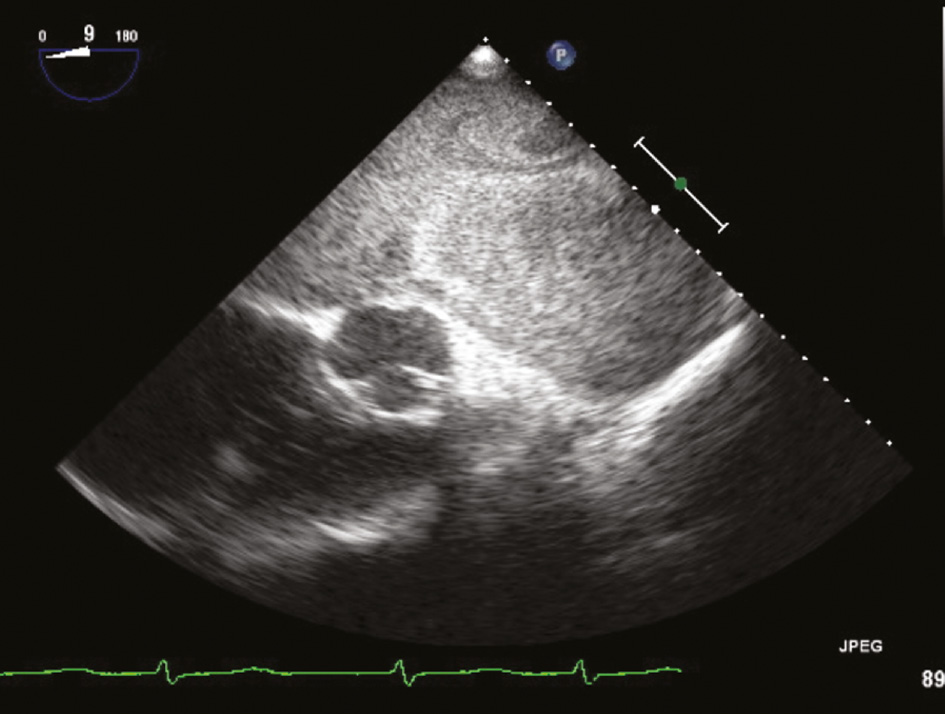

Both ECLS implantation and interhospital transfer were implemented without complications. In the further course, preventing thromboembolic complications while at the same time controlling an increasingly dramatic hemorrhagic tendency turned out to be a challenge. ECG showed spontaneous contrast/sludge in the left atrium (Figure 3), although the patient’s initial international normalized ratio (INR) of 3.3 was accompanied by moderate thrombocytopenia and his partial thromboplastin time (PTT) was 50.2 s after receiving 2000 IU unfractionated heparin for ECLS implantation. Over the next 2 days, his INR climbed to 8.9 and extensive spontaneous oropharyngeal, pulmonary, and gastrointestinal bleeding required transfusion of several units of packed red blood cells and moderate correction of his coagulation status.

ECG view of GLA with spontaneous contrast/sludge.